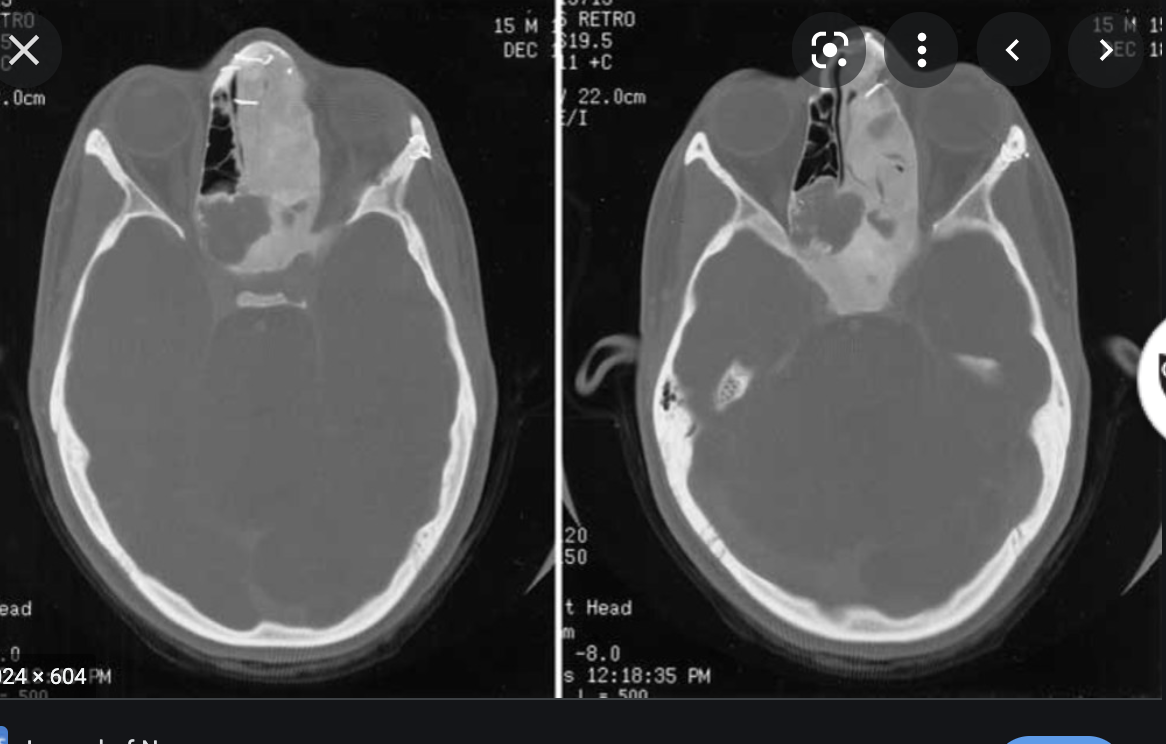

Central skull base Aneurysms